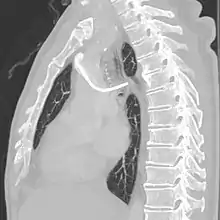

A port consists of a reservoir compartment (the portal) that has a silicone bubble for needle insertion (the septum), with an attached plastic tube (the catheter). The device is surgically inserted under the skin in the upper chest or in the arm and appears as a bump under the skin. It requires no special maintenance other than occasional flushing to keep clear. It is completely internal so swimming and bathing are not a problem. The catheter runs from the portal and is surgically inserted into a vein (usually the jugular vein or less optimally the subclavian vein). Ideally, the catheter terminates in the superior vena cava or the right atrium. This position allows infused agents to be spread throughout the body quickly and efficiently.

The port is then sutured on two sites to the underlying muscles. The tip of the catheter is checked for kinks and position using a fluoroscope. Besides that, aspiration of blood and contrast injection through the chemoport can also be used to confirm the position. The port is the closed in two layers (subcutaneous tissue is sutured first, followed by the skin). Sterile dressing is then placed on the port.[3] The optimum site to park the tip of the catheter is at the cavo-atrial junction or with margin of error of not more than 4 cm above the junction.[3]

A follow-up on a chest radiograph can immediately detect complications associated with the procedure such as pneumothorax, hemothorax and malpositions of the catheter. However, routine chest radiography is not needed due to the low complication rates associated with the procedure. The chest radiograph is only done if there is clinical suspicion of a complication.[4]